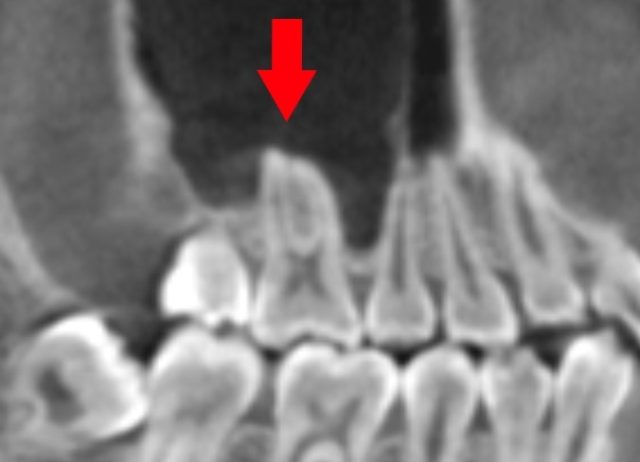

歯性上顎洞炎に なりやすい人 なりにくい人

歯性上顎洞炎になりやすい人

歯根と、上顎洞が近い人です。

上は、上顎洞内に、

大臼歯の歯根が

飛び出しています。

もし、この根が化膿すると、

上顎洞に炎症が波及しやすいでしょう。

この様な方は、

歯性上顎洞炎になりやすいと思われます。

歯性上顎洞炎になりにくい人

上は、上の大臼歯の歯根と、

上顎洞の距離がある方です。

もし、歯根が化膿しても、

炎症は、上顎洞へは、波及しにくいでしょう。

歯性上顎洞炎には、なりにくいと思われます。